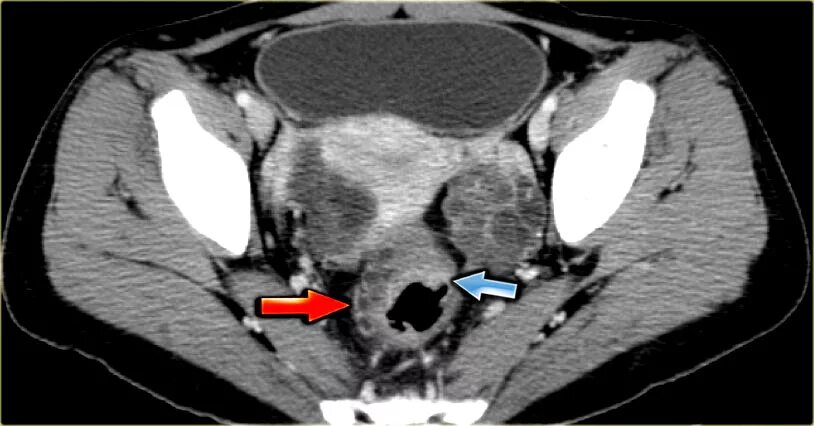

Солидное образование в малом тазу